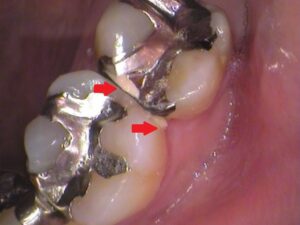

歯と歯の間にデンタルフロスを通してみると、

何か白いものが出てきました。

これですね。

歯垢(プラーク)といって細菌の塊であったり、

食べかすであったり、

銀歯のつなぎ目に汚れが溜まってしまっています。

歯ぐきの中で細菌が繁殖し、歯ぐきが炎症を起こしていますので、

歯ぐきからの出血も出てきます。

銀歯が不適合(歯に合わずズレていること)

になっていると、食べ物が詰まりやすく、詰まった場所には細菌が繁殖し、虫歯や歯周病の原因になります。